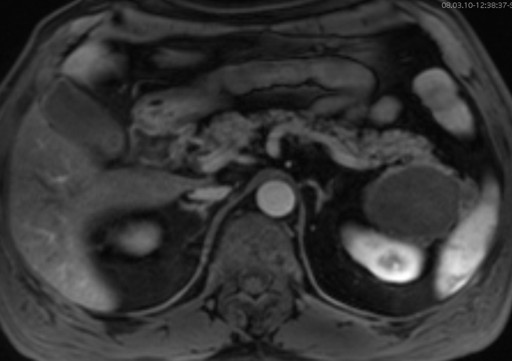

A 63-year-old man with a previous history of colon cancer, resected 3 years earlier, presented for a routine clinical follow-up. Physical examination and past medical history were unremarkable, except for an appendectomy at the age of 15. The patient had had a history of intermittent and mild left upper quadrant abdominal pain not associated with meals before a resection for colonic cancer; CA 19-9, CEA and amylase were unremarkable. There was no body weight loss or fever, and the patient had no previous history of pancreatitis. An abdominal ultrasound was performed which showed a 7 cm non homogeneous anechoic mass at the level of the pancreatic tail. An MR scan was subsequently obtained which confirmed the presence of a 7x4 cm lesion at the level of the pancreatic tail, close to the splenic hylum. This lesion showed a complex structure with multiple sub-centimeter nodules within it. In particular, the lesion was homogeneously hypointense on the pre-contrast T1-weighted MR images (Figure 1), showing a mild rim of enhancement after intravenous contrast administration while maintaining the hypointensity of the central core constant (Figure 2); on T2-weighted MR images, the pancreatic mass had a "cheerios-like" appearance, showing multiple small nodules with a central hypointensity and peripheral hyperintensity; a fluid-level was also present at the bottom of the lesion (Figures 3 and 4), most likely reflecting the inflammatory changes of the lesion. The patient subsequently underwent a distal pancreatectomy and splenectomy (due to the proximity of the lesion to the splenic hylum). Histological examination demonstrated the benign nature of the lesion consisting of a pancreatic lymphoepithelial cyst. The surface of the cyst was smooth, the lesion was filled with keratinous material and the walls were lined with stratified squamous epithelium which was surrounded by a layer of lymphoid tissue composed of small lymphocytes, plasma cells and germinal centers, without signs of atypia (Figure 5). The periphery was composed of normal pancreatic tissue. The postoperative course was uneventful and the patient was discharged from the hospital 10 days after the surgical intervention.

Figure 2. Post-contrast axial-T1-weighted MR image showing a mild rim of enhancement of the pancreatic mass, with constant hypointensity of the central core. |